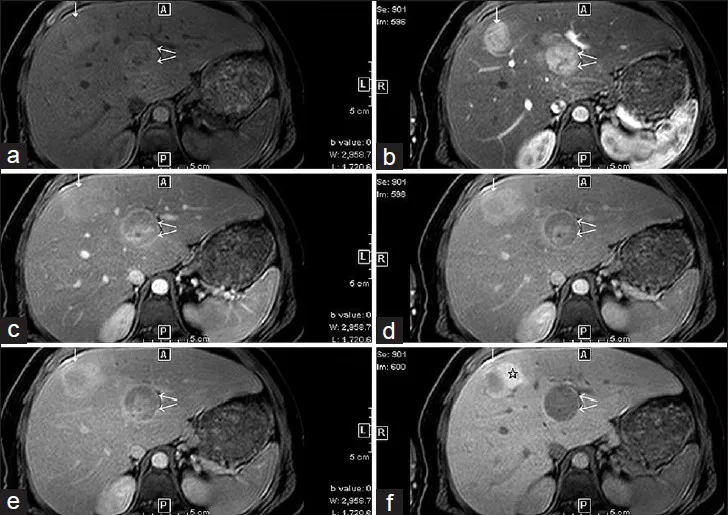

- Hepatic: Hepatic adenomas (GSD I) → risk of hemorrhage or malignant transformation to HCC.

⭐ In GSD I, hepatic adenomas can regress with strict dietary therapy, but the risk of malignant transformation into hepatocellular carcinoma (HCC) remains a lifelong concern.